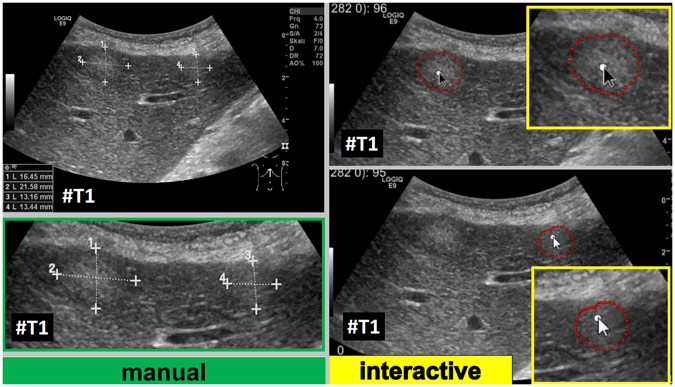

Adjustment of the segmentation algorithm using liver metastases with different echo pattern

Our segmentation algorithm was integrated into the medical prototyping platform MeVisLab (Fraunhofer MeVis, Bremen, Germany, www.mevislab.de) as a C++ module33, 34. The interactive real-time segmentation could be performed smoothly on a Macbook Pro laptop with an Intel Core i7-4850HQ CPU @ 2.30 GHz, 16 GB RAM and Windows 8.1 Professional installed. The adjustment of our segmentation algorithm was done using a set of liver metastases with different echo pattern. For visual inspection, Fig. 7 shows an interactive and a manual segmentation result of a liver metastasis (metastasis of a colon cancer) that appears brighter (hyperechoic), when compared to the surrounding liver tissue. Further, the metastasis has a darker (hypoechoic) halo and exhibits a very low contrast to the surrounding liver parenchyma. Overall, the leftmost image of Fig. 7 presents the native acquisition with a zoomed area of the metastasis. The image in the middle of Fig. 7 shows the manual measurement result of the metastasis (white dotted line between two crosses). Finally, the rightmost image of Fig. 7 presents the interactive segmentation results and the user-defined seed point at this position (red dots and white dot, respectively). In Fig. 8, the interactive segmentation results of several liver metastases (red dots) are presented as follows: Upper Left: a metastasis of a neuroendocrine neoplasm of the pancreas. Upper right: a metastasis of a colon cancer. Lower images: two different views of a metastasis of a uveal melanoma. Compared to the surrounding liver tissue, the metastasis in the upper left image appears brighter (hyperechoic). In contrast, the two metastases in the lower images appear darker (hypoechoic) when compared to the surrounding liver tissue. Finally, the metastasis of the upper right image has bright and dark areas in comparison to the surrounding areas. For all segmentation results of Fig. 8, the white dots represent the corresponding seed points. At these positions, the user was satisfied with the borders of the lesion and stopped the interactive segmentation process by releasing the mouse button.

Segmentation results (manual/interactive) of a hyperechoic appearing metastasis with a hypoechoic halo (metastasis of a colon cancer), where the metastasis shows a very low contrast to the surrounding liver parenchyma. The native image with a zoomed view of the metastasis is presented in the left image. A manual measurement of the maximal metastasis diameter (white dotted line between two white crosses) is shown in the middle image. Finally, the rightmost image presents the interactive segmentation results (red dots) with the corresponding user-defined seed point (white). Note: figure adapted from26.

Figure 9 presents several screenshots from a video, where two metastases of a colon cancer35 in one image were segmented interactively (from the top to the bottom). The upper image presents the native acquisition. The next image presents the position of the mouse cursor where the user started the interactive segmentation. The third image presents the first segmentation result (red dots) at the position of the mouse cursor. In the following image, the user moved the seed point (white dot) for the segmentation slightly to the right to get a better segmentation. After being satisfied with the segmentation of the first metastasis, the user moved the seed point to the second metastasis on the right. As seen in the screenshots of the video, the resulting segmentation contours (red dots) collapsed, because, in this area, no lesion is present (note: the screenshots present only a fraction of the whole video). When the user reached the second metastasis on the right, the red segmentation contour automatically expanded again and adapted to the metastasis border (lower two images). The lower image presents the final outlining of the second metastasis, where the user stopped the interactive segmentation process. Moreover, Fig. 10 shows a side-by-side comparison of manual expert measurements (left) and interactive segmentation results (right) for the two liver metastases from Fig. 9.